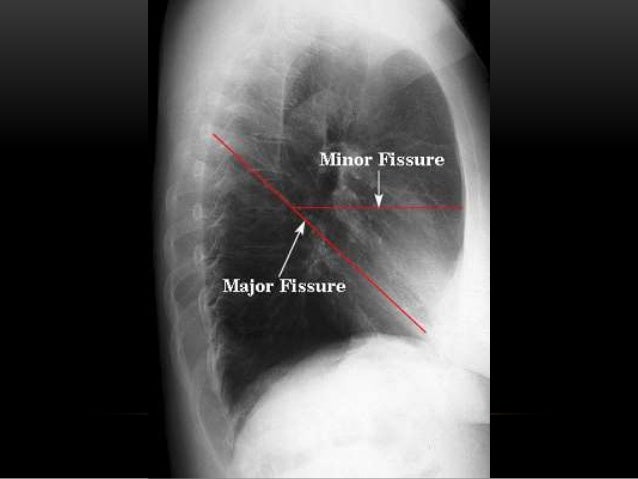

Анатомические изображения сегментов легких различных животных

Раздел: Другие животные